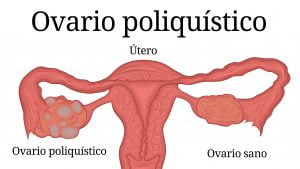

¿Sabías que 1 de cada 10 mujeres sufren de ovarios poliquísticos?

El síndrome de ovarios poliquísticos es la causa más común de infertilidad. Entonces, quisieras ser madre, pero no sabes si padeces de ovarios poliquísticos, estos son los síntomas más comunes:

- Menstruaciones irregulares.

- Infertilidad.

- Dolor pélvico.

- Exceso de vello en la cara, el pecho, el abdomen o los muslos.

- Subida de peso.

- Acné o piel grasosa.

- Parches de piel gruesa de color marrón o negro.

Los niveles de AMH se correlacionan con la gravedad de los síntomas del SOP. El síndrome de ovario poliquístico es más común en las mujeres que tienen obesidad o que tienen una madre o hermana con síndrome de ovario poliquístico.